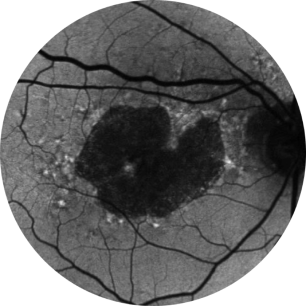

Avaliação inicial Ano 1

BCVA 20/63+, área de AG de 5,18 mm2

Avaliação inicial Ano 2

BCVA 20/80-2, área de AG de 10,39 mm2

Avaliação inicial Ano 5

BCVA 20/200, área de AG de 18,58 mm2

As imagens são cortesia do Dr. David Elchenbaum, da Retina Vitreous Associates of Florida.

BCVA = melhor acuidade visual corrigida (best corrected visual acuity).